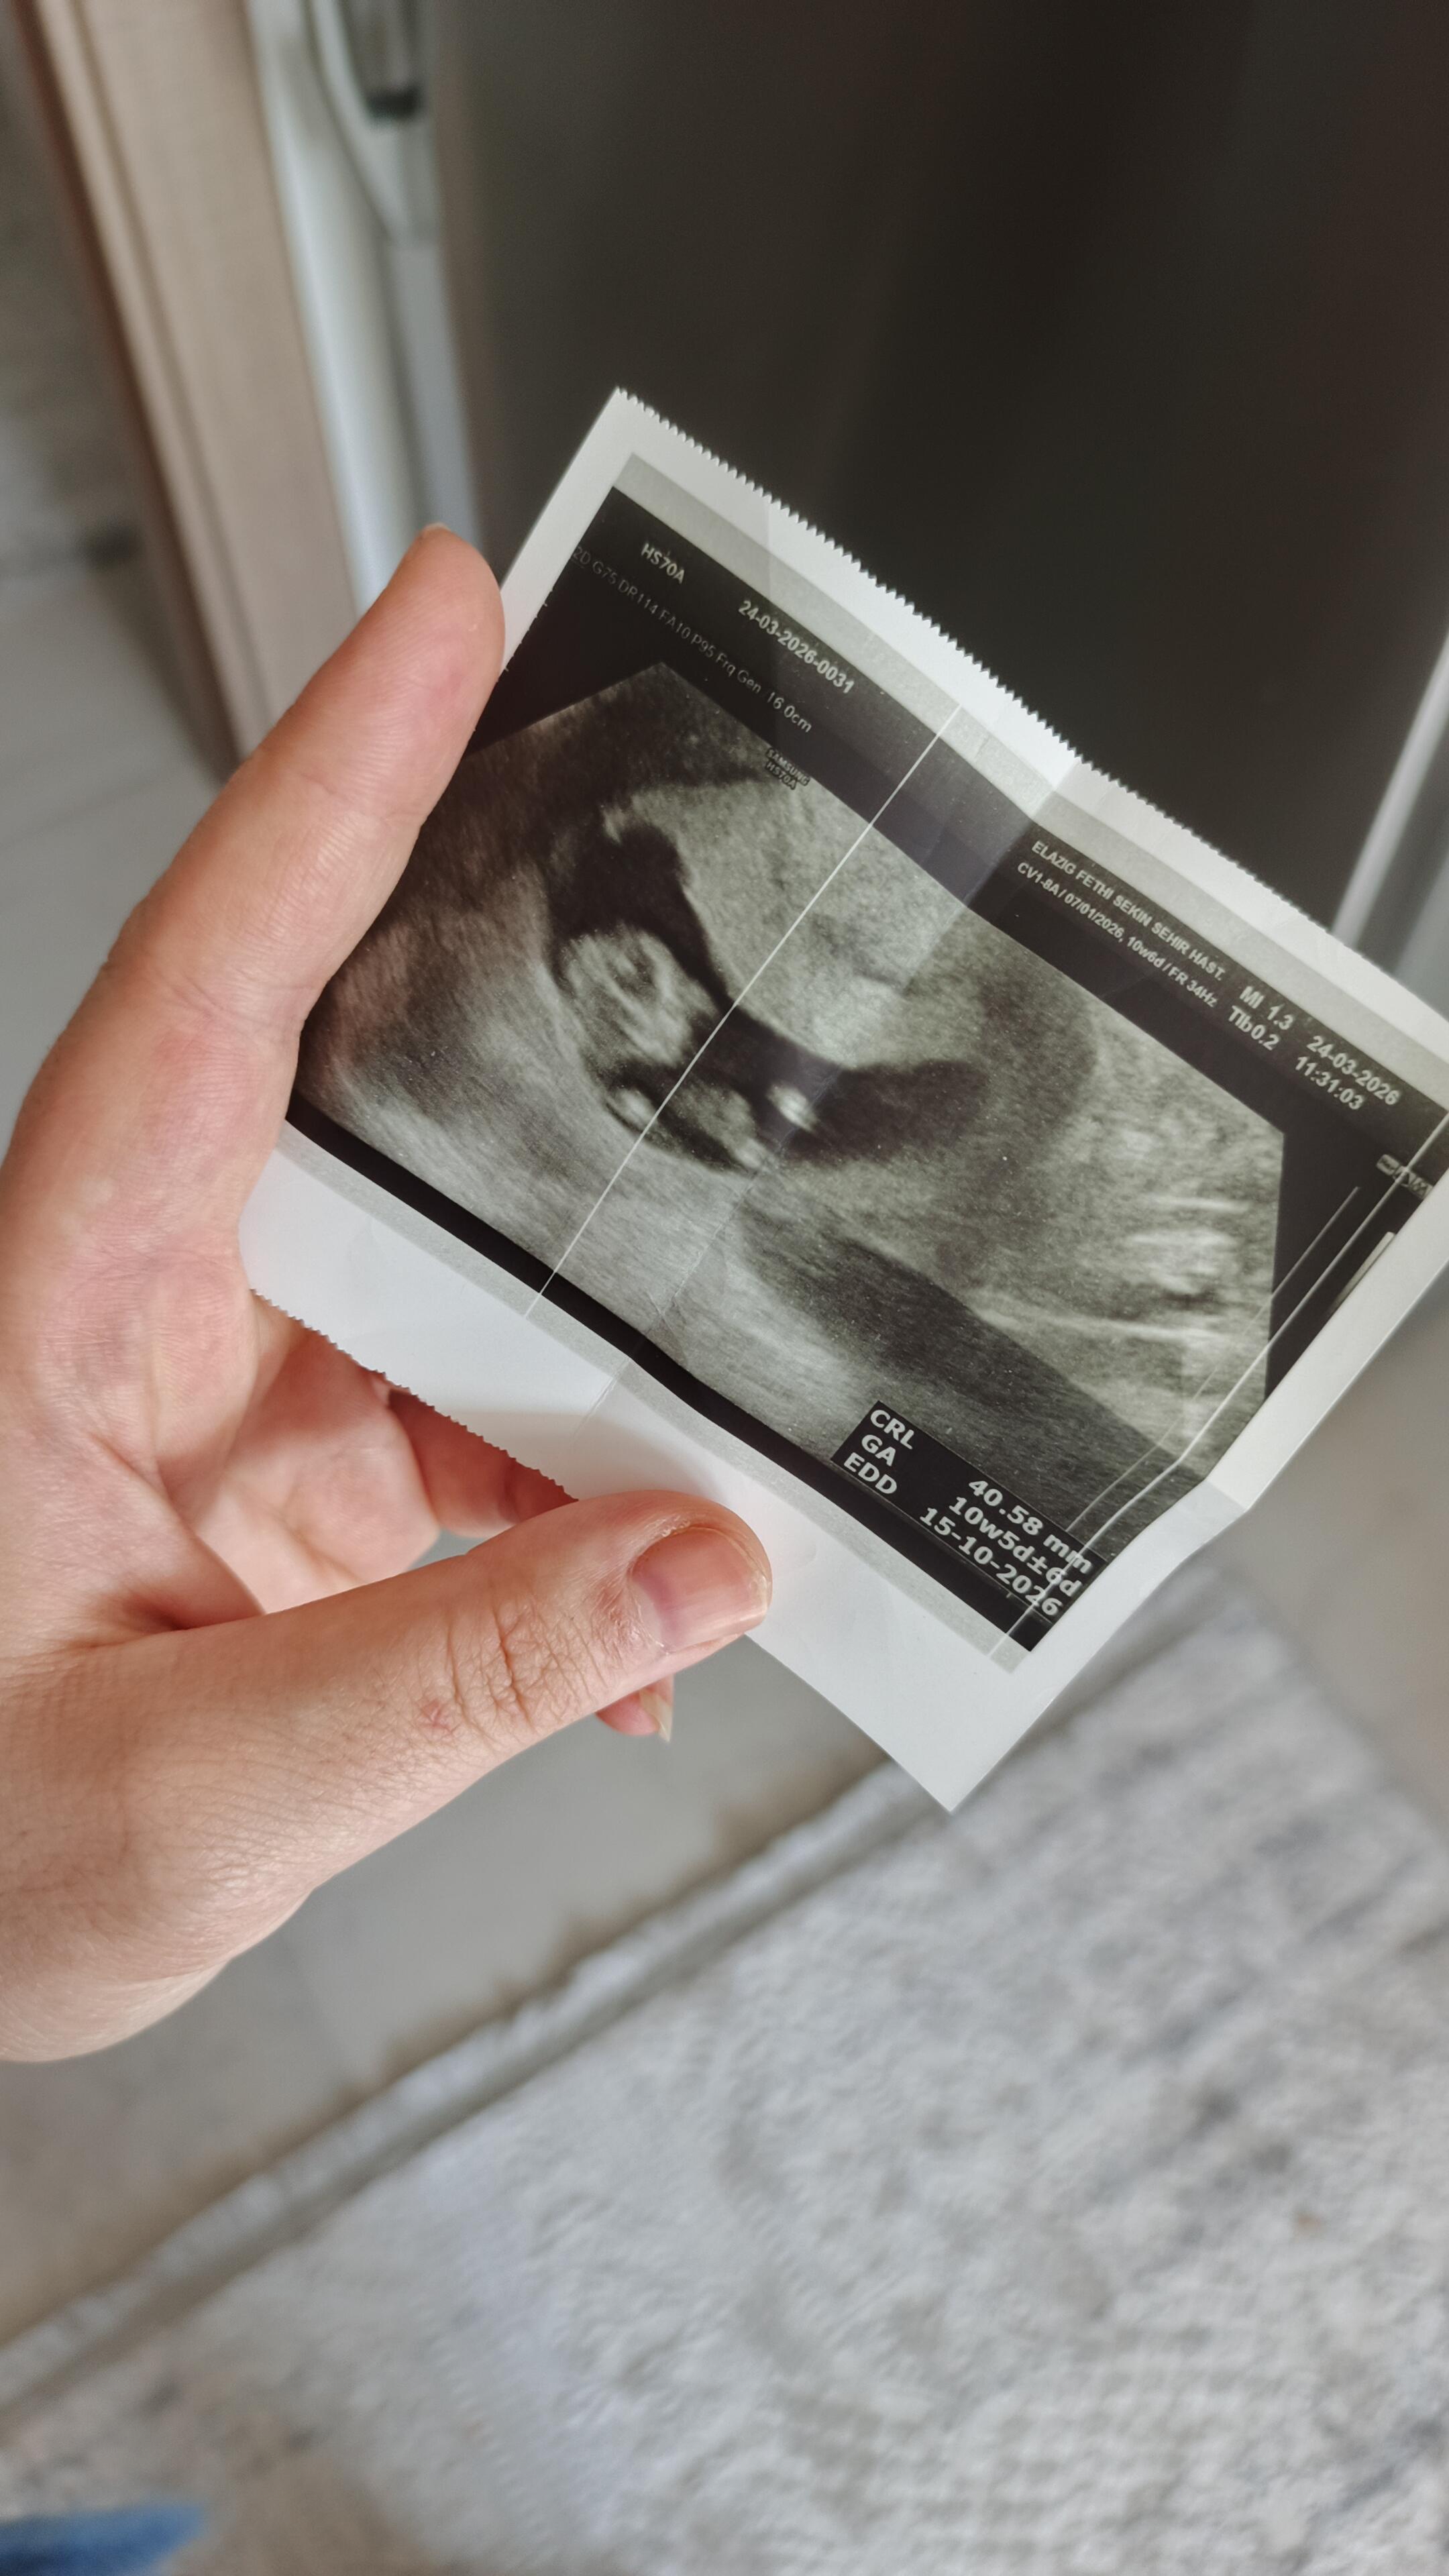

Ay Devlet hastanesindeki doktor kiza benziyor dedi bakalim

ama galiba sizzle haftamiz günümüz aynı

cinsel organı düz 80 derece aşağına bence kız